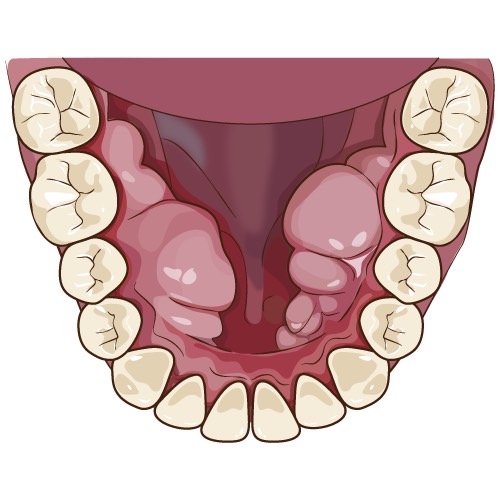

下顎隆起

口蓋隆起

歯槽隆起